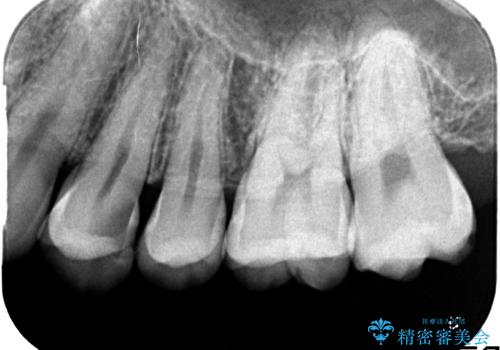

気づかないうちに大きな虫歯が 神経を保存し、セラミックで修復

- 神経を温存し、セラミックインレーによる修復をおこなった。

深い虫歯があった場合、たとえ神経を温存できたとしても長期的には痛みが出てきたり、神経がいつの間にか失活(正常な反応を失う)してしまったりするリスクはあります。

安易に神経を取り除くべきではありませんが、神経を保存するのであればそのようなリスクをよく理解していただく必要があります。

詰め物の種類:e.max press